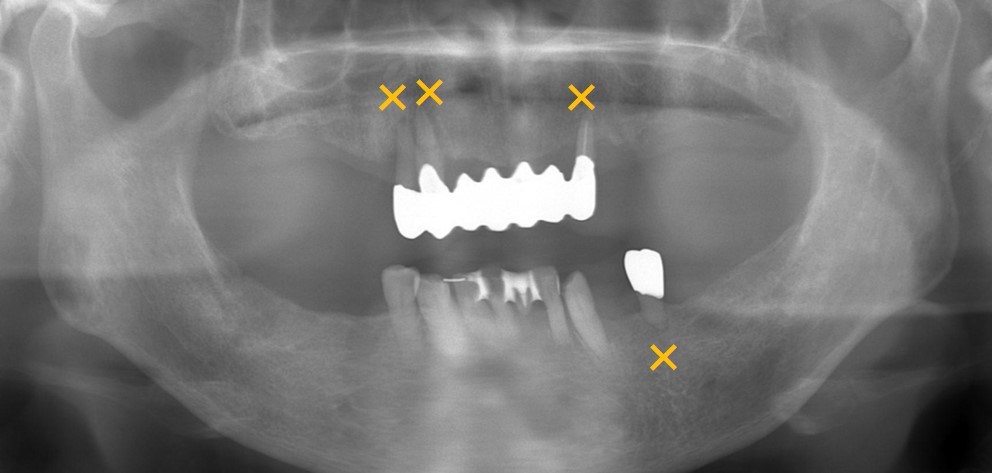

レントゲン写真です。×の歯は動揺が激しく重度の歯周病にり患しているため抜歯となります。